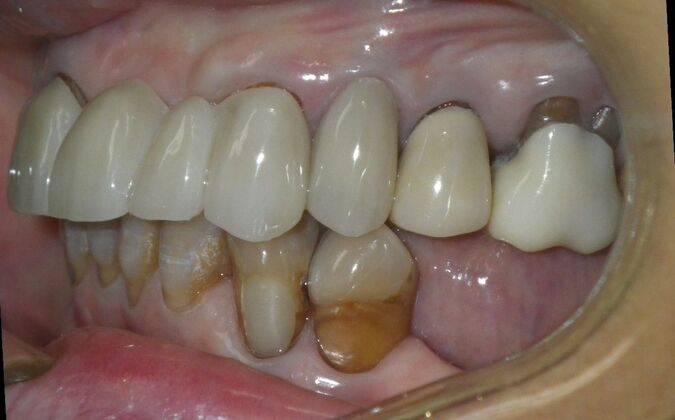

Cosmetic Changes with Veneers and Crown and Bridge: Case 6

Description

This patient had long term acidic erosion of upper and lower teeth eventually leading to loss of upper left central and lateral incisors. While she was somewhat happy with replacement of her front teeth with a removable appliance, she really desired to have something she didn't have to remove. So patient opted to be conservative with two single unit crowns as well as a four unit anterior bridge. These were fabricated using all ceramic without metal